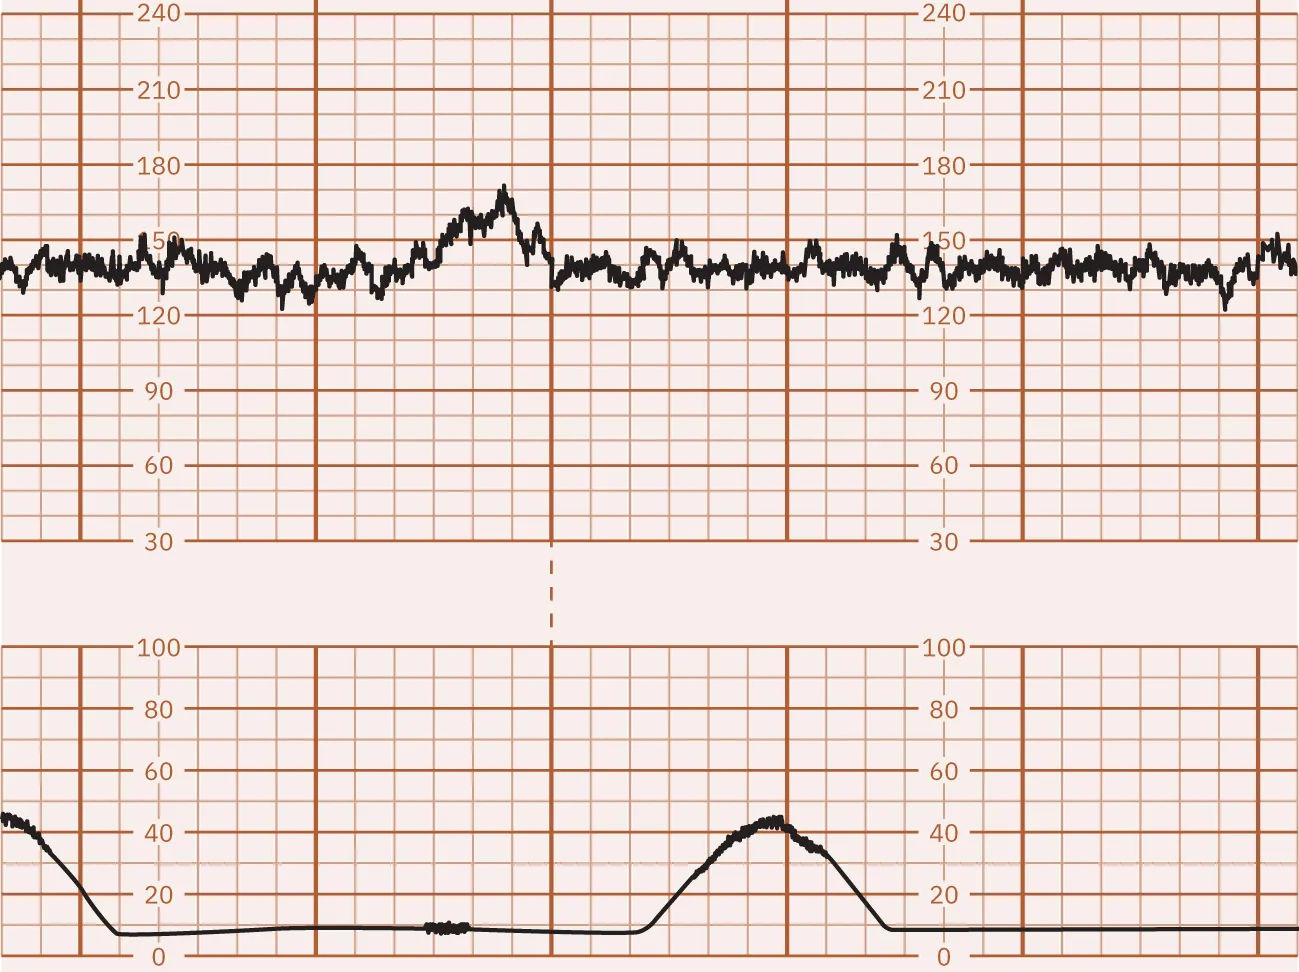

Marked FHR Variability

A FHR baseline fluctuation greater than 25 bpm is considered marked FHR variability. Because of the extreme fluctuations, the FHR baseline is undeterminable. Marked FHR variability suggests hypoxia and is usually seen during the second stage of labor. Marked variability requires further assessment to determine the cause and notification of the health-care provider. Figure 16.8 shows a monitor tracing that indicates marked variability.

Fetal heart rate reading indicating marked variability.

Figure 16.8 Marked FHR Variability This monitor tracing shows marked FHR variability with greater than 25 bpm. (attribution: Copyright Rice University, OpenStax, under CC BY 4.0 license)